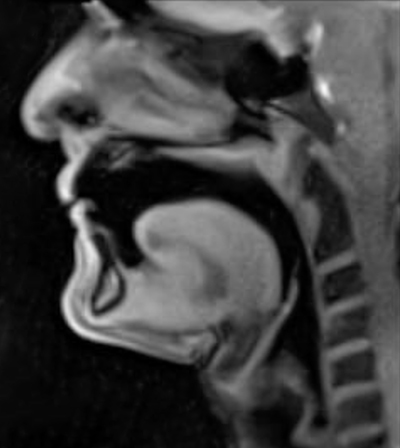

Trombone Science will be launched in 2026. This site will feature real-time MRI (magnetic resonance imaging) videos of Douglas Yeo playing on a specially made trombone manufactured and donated to the MRI project by YAMAHA Corporation, Japan, and commentary by Douglas Yeo and Dr. Peter Iltis. These videos were recorded in 2017 and 2025 at the Max Planck Institute, Göttingen, Germany, as part of the MRI Brass Repository Project. Viewers will see the actual real-time workings of the mouth and tongue (oral cavity/oropharynx), the throat, trachea, and glottis, and the chest and lungs (thoracic cavity) during trombone playing. Trombone Science will show and discuss how human body works during trombone playing throughout the breathing process and when a player produces articulations, slurs, notes in various registers, and more. Trombone Science will also include links to scientific articles based on the work of the MRI Brass Repository Project, and it will provide unique insights for both performers and teachers.